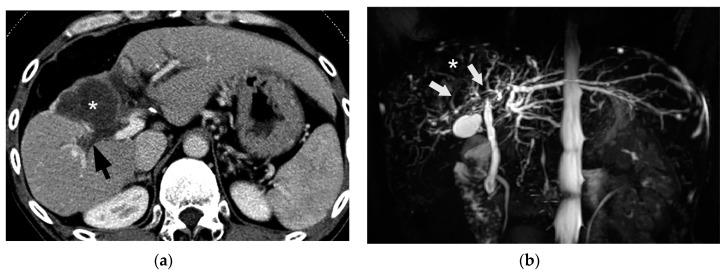

Bile duct necrosis (BDN) with biloma formation is a type of ischemic bile duct injury that is one of the serious complications associated with transarterial therapies, such as transcatheter chemoembolization therapy (TACE), and radioembolization for hepatocellular carcinoma (HCC) and hepatic arterial infusion chemotherapy (HAIC) for metastatic liver cancer from colorectal carcinoma. In terms of the occurrence of BDN and subsequent biloma formation, ischemic injury to the peribiliary vascular plexus (PBP), the supporting vessel of bile duct epithelium, is thought to be intimately associated. In this paper, we first describe the anatomy, blood supply, and function of the intrahepatic bile duct, and then illustrate the pathophysiology of BDN, and finally present the imaging findings of BDN. Under the process of BDN formation, ischemia of the PBP induces the disruption of the bile duct epithelial protection mechanism that causes coagulation and fibrinoid necrosis of the surrounding tissue by the detergent action of exuded bile acids, and eventually a biloma forms. Once BDN occurs, persistent tissue damage to the surrounding bile duct is induced by imbibed bile acids, and portal vein thrombosis may also be observed. On pre-contrast and contrast-enhanced computed tomography (CT), BDN shows similar findings to intrahepatic bile duct dilatation, and, therefore, it is sometimes misdiagnosed. Differentiation of imaging findings on CT and ultrasound (US)/magnetic resonance (MR) imaging/MR cholangiopancreatography (MRCP) is important for correct diagnosis of BDN.

伴有胆汁瘤形成的胆管坏死(BDN)是一种缺血性胆管损伤,是经动脉治疗相关的严重并发症之一,如经导管肝动脉化疗栓塞术(TACE)、肝细胞癌(HCC)的放射性栓塞以及结直肠癌肝转移的肝动脉灌注化疗(HAIC)。就BDN的发生及随后胆汁瘤的形成而言,胆管周围血管丛(PBP)(胆管上皮的支持血管)的缺血性损伤被认为与之密切相关。在本文中,我们首先描述肝内胆管的解剖结构、血液供应和功能,然后阐述BDN的病理生理学,最后介绍BDN的影像学表现。在BDN形成过程中,PBP的缺血会导致胆管上皮保护机制的破坏,渗出的胆汁酸通过去污剂作用导致周围组织发生凝固性坏死和纤维蛋白样坏死,最终形成胆汁瘤。一旦发生BDN,吸收的胆汁酸会导致周围胆管持续的组织损伤,还可能观察到门静脉血栓形成。在平扫及增强计算机断层扫描(CT)上,BDN表现与肝内胆管扩张相似,因此有时会被误诊。CT及超声(US)/磁共振(MR)成像/磁共振胰胆管造影(MRCP)上影像学表现的鉴别对于BDN的正确诊断很重要。